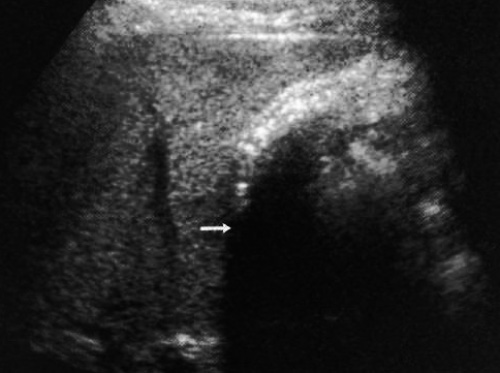

Фото 4. Холелитиаз. А – УЗИ в продольной плоскости, пациент находится в положении лежа: стрелкой обозначен мелкий эхогенный очаг без тени, локализованный в шейке желчного пузыря. В – УЗИ того же пациента в положении лежа на правом боку: стрелками обозначены камни в желчном пузыре